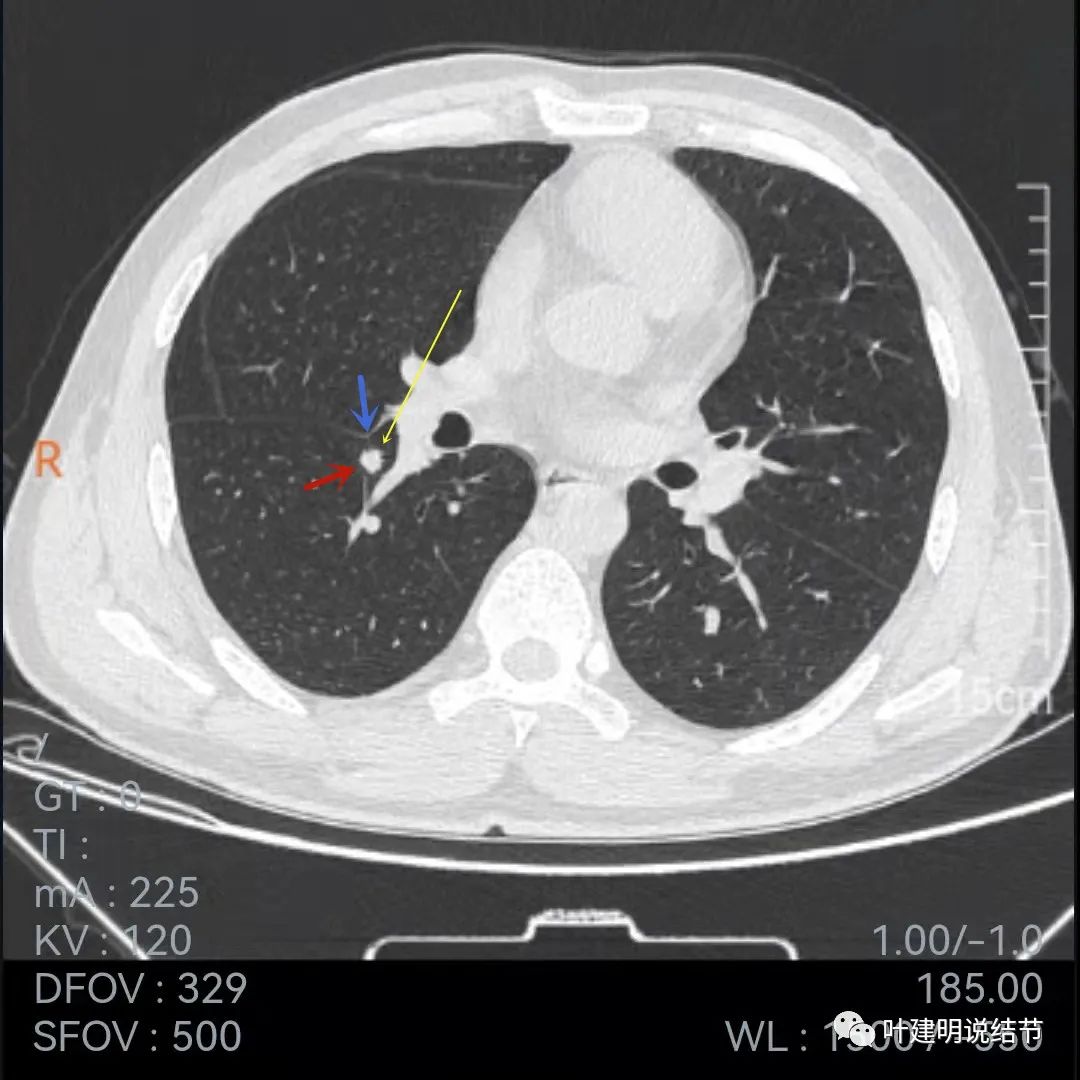

我们再来看2019年的片子:

上面是2019年5月份的片子,不是薄层,只有这两个层面见到病灶,是实性小结节,叶间裂似略有牵拉,病灶边缘比较光滑,密度相对较均匀,没有毛刺或血管征,单看应该良性结节可能性大,至少先随访。